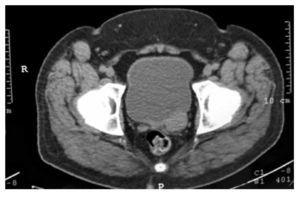

Hombre de 37 años de edad, con antecedente de diabetes mellitus tipo 2, tratado con insulina (20 U de intermedia y 15 U de rápida). El padecimiento actual inició 7 días previos a acudir a valoración, consistente en dolor lumbar irradiado a flanco y fosa ilíaca izquierda, tipo cólico, de moderada intensidad, continúo. Al examen físico, tacto rectal con próstata adenomatosa grado 1, no sospechosa. Se realizó ultrasonido (USG) renal y suprapúbico, donde se encontró imagen sugestiva de lesión paravesical izquierda, hiperecoica, homogénea, de bordes bien definidos, de 2 x 2 cm (fig. 1). La urotomografía (UroTAC) corrobora imagen de lesión, con densidad sólida entre base de vejiga y vesícula seminal izquierda de 3 x 2 cm (figs. 2 y 3). El USG transrectal con lesión dependiente de vesícula seminal izquierda (fig. 1). En la cistoscopía diagnóstica se encontró compresión extrínseca parameatal izquierda. Se llevó a cabo resección de neoplasia de vesícula seminal izquierda por vía laparoscópica de 3 x 2 cm (fig. 4), con resultado de histopatología de leiomioma de vesícula seminal. El paciente se encuentra en seguimiento con buena evolución.

Figura 1 Ultrasonido transrectal. Se identifica una lesión paravesical posterior, en el sitio de la vesícula seminal.